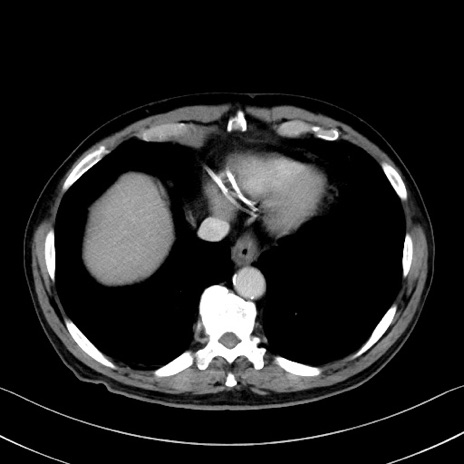

症例35(横断像)

【症例】70歳代 男性

【主訴】腹部膨満、嘔吐

【現病歴】昨日より腹部膨満感出現。本日増悪し、仙痛出現。嘔吐あり、受診。

【既往歴】糖尿病、胆摘後

【身体所見】BP 149/80mmHg、HR 74/min、BT 35.9℃、腹部:膨満、軟、圧痛なし。腸雑音減弱あり。上腹部正中切開瘢痕あり。

【データ】WBC 13500、CRP 1.72